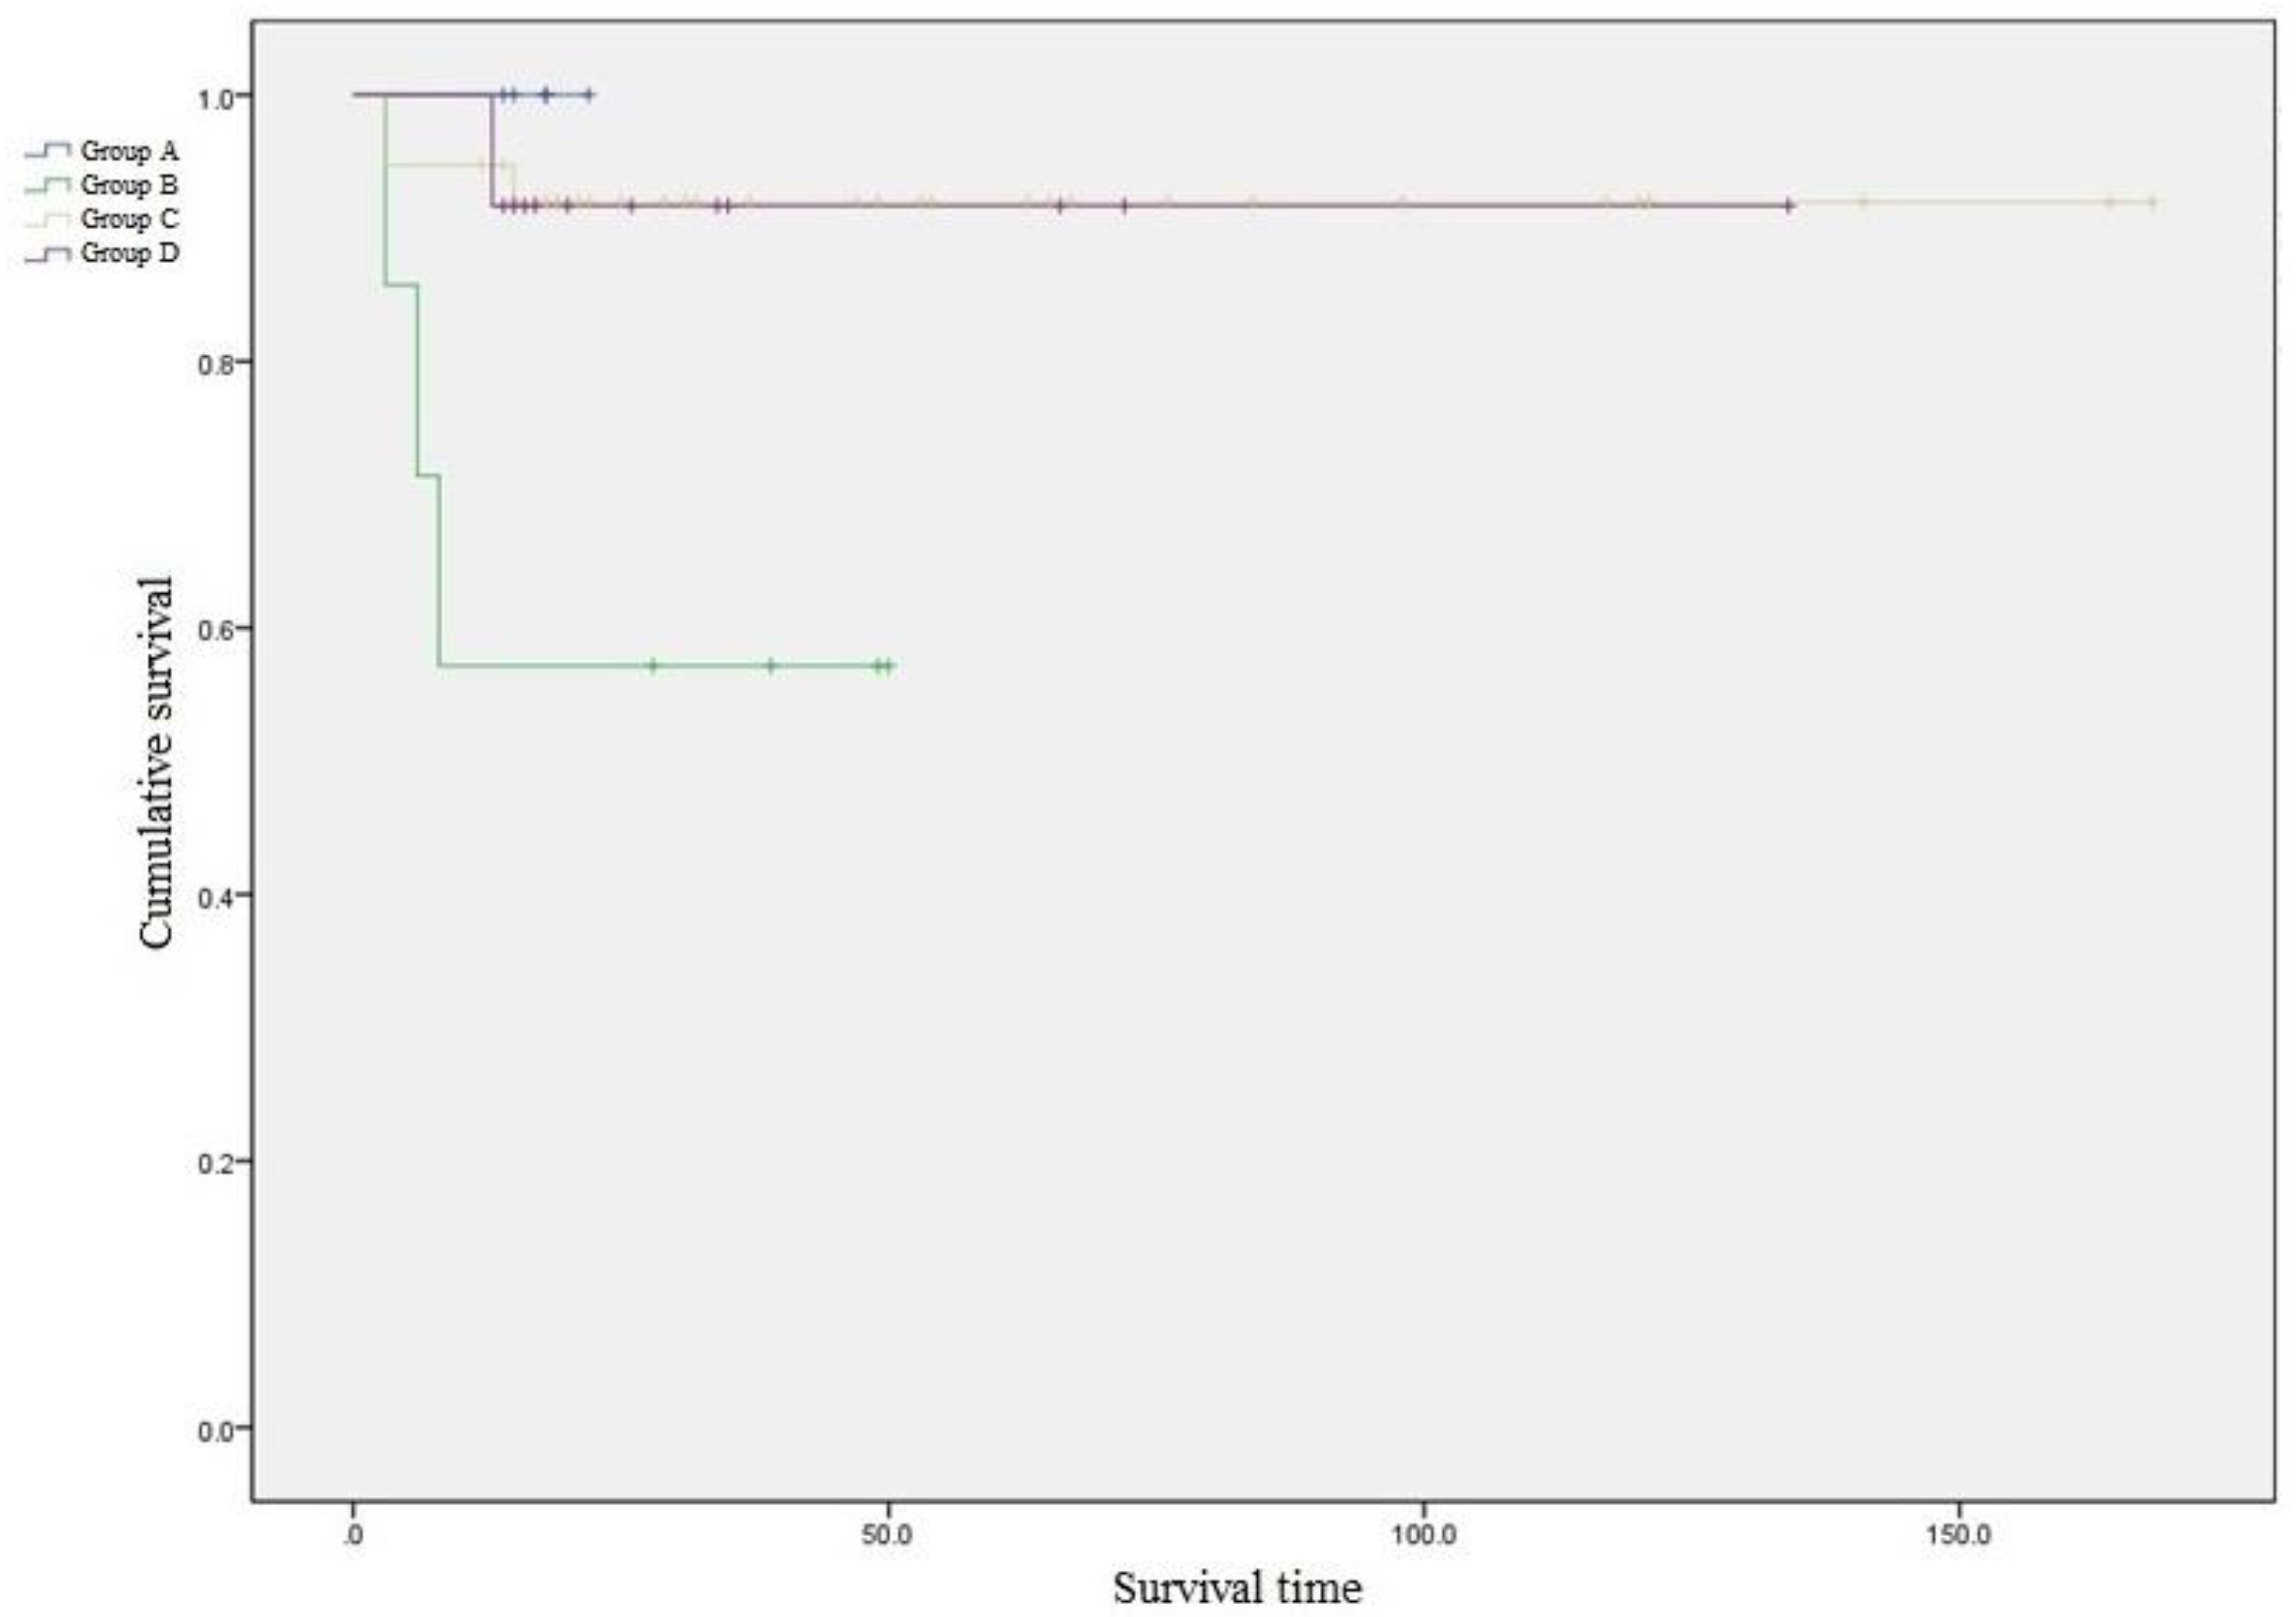

Seven cases of failure in 63 patients occurred during the follow-up period due to non-union, malunions, hardware failure, infection, or reoperations. Kaplan–Meier survival analysis comparing the four groups with the endpoint as complications developing due to any reason showed significant differences between the groups (log-rank test

p = 0.010) (

Figure 3).